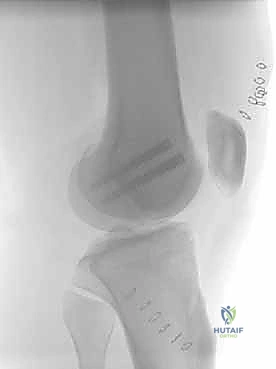

- الأشعة السينية (X-Rays): أخذ صور من زوايا متعددة (أمامي خلفي، وجانبي) لتحديد موقع الكسر ونوعه.

المرحلة الرابعة: التثبيت النهائي بالشرائح والمسامير (Fixation)

يتم استخدام "شرائح الإغلاق التشريحية" (Anatomical Locking Plates) المصنوعة من التيتانيوم عالي الجودة. هذه الشرائح مصممة خصيصاً لتأخذ شكل الجزء السفلي من عظم الفخذ. يتم تمرير الشريحة أسفل العضلات وتثبيتها بمسامير تغلق داخل الشريحة نفسها (Locking Screws)، مما يوفر ثباتاً ميكانيكياً هائلاً، حتى في حالات العظام الهشة.